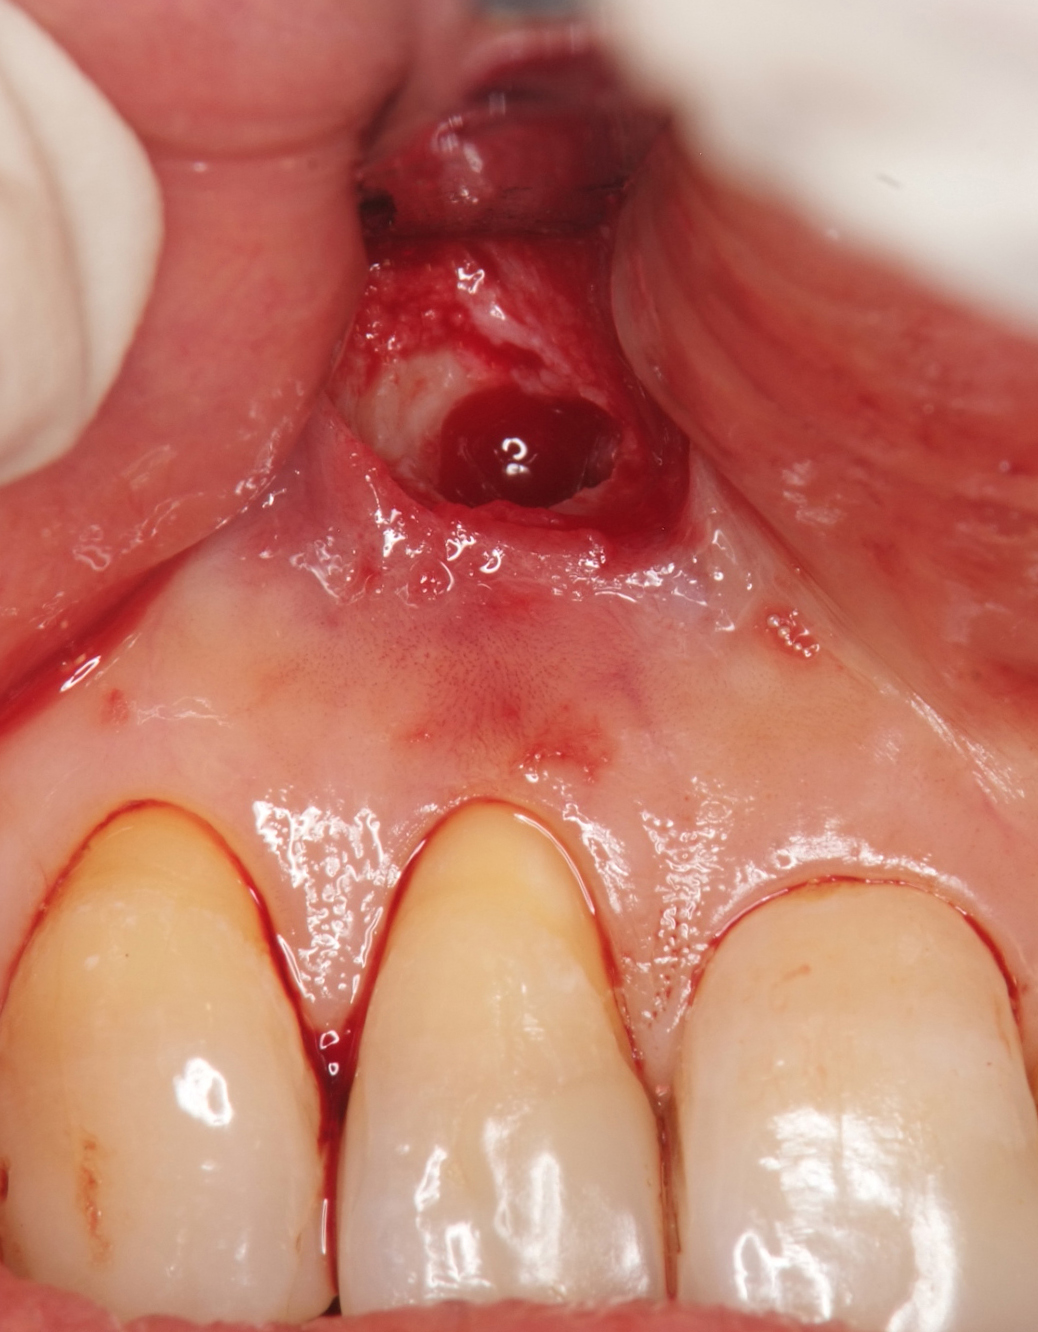

図2a 下顎中切歯の根尖病変. かなり大きいレントゲン透過像